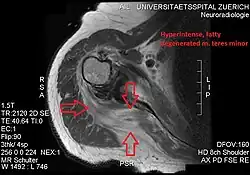

Imaging

Conjoint and intact tendon disc of teres minor and infraspinatus muscle.

Intact teres minor tendon with physiologically hypointense signal.

Hyperintense, fatty degenerated teres minor muscle.

Ultrasonography is a tool to detect a fatty degenerative atrophy of the teres minor and shows in affected muscles increased echogenicity and betimes a slight reduction in muscle bulk. MR imaging helps to consolidate the diagnosis of neurogenic muscle atrophy. Extracellular edema after traumatic events causing neural damage show an increased signal intensity on T2-weighted MRI sequences and normal intensity on T1-weighted sequences. Posterior humeral circumflex artery compression and reduced blood flow in stressful arm positions and or maneuvers can be diagnosed by a Doppler ultrasonography. The nerve should be detected adjacent to the vessel. In an elevated arm position the axillary neurovascular bundle can be seen at the posterior axillary fold just before it perforates the deltoideus, while the posterior course is well visible in the neutral position. For a detailed assessment of the artery, a MR angiography is required. The major task of an ultrasonographic examination is to rule out any space occupying mass. Additional electromyography is helpful to reveal any decelerated nerve conduction velocity, and thus denervation of the concerned muscle.[6]